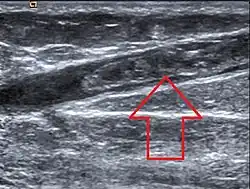

| Ultrasonographic image showing thrombosis of the great saphenous vein. | |